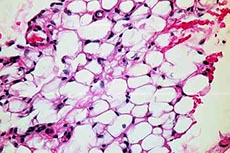

Pembuluh darah pecah terjadi ketika bekuan terbentuk di dalam pembuluh darah. Saat darah melewati gumpalan itu menyebabkan pembuluh darah itu sendiri untuk tonjolan dari tekanan ditambahkan. Ketika pembuluh darah menjadi lemah pada akhirnya dapat mematahkan terbuka, menyebabkan darah untuk melarikan diri. Hal ini dapat terjadi di kedua pembuluh darah kecil dan arteri besar. Sebuah pembuluh darah pecah di mata adalah ketika hal ini terjadi di pembuluh darah kecil pada mata. Hasilnya adalah baik titik merah atau kemerahan seluruh mata secara keseluruhan. Pembuluh darah kecil di mata rentan pecah karena ukuran mereka.